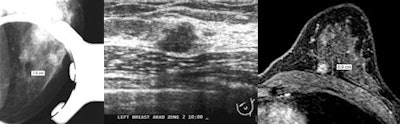

| Images demonstrate discrepancies in lesion measurements across different imaging modalities. At left, FFDM image at 1.6X magnification shows PACS software caliper tool indicating lesion size of 1.9 cm. In center, ultrasound of same lesion shows lesion size of 1.0 cm. At right, breast MR image of same lesion indicates size is 0.9 cm. Images courtesy of the American Roentgen Ray Society. |

The researchers found that the electronic calipers on the PACS review workstation measured the lesion at 1.9 cm in 1.6X magnification mode. However, the same mass measured 1.0 cm on ultrasound and 0.9 cm on breast MR images, and pathologic evaluation revealed a 0.9-cm invasive ductal cancer.